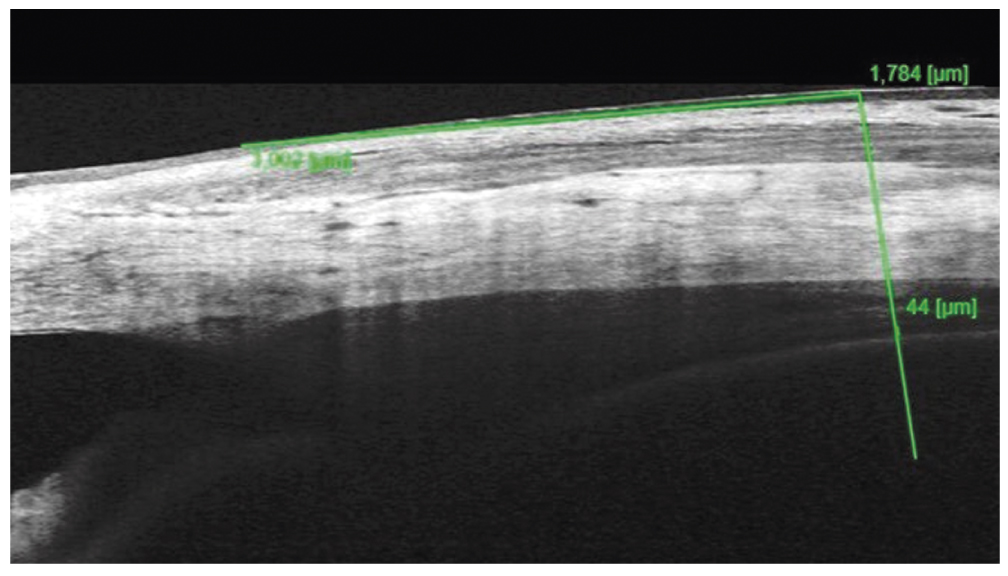

ОКТ переднего отрезка глаза по предлагаемому способу. OD: толщина сосудистого слоя цилиарного тела во внутреннем отделе 30 мкм (рис. 5), в наружном отделе — 31 мкм; OS — 32 мкм и 34 мкм соответственно; ОКТ заднего отрезка глаза без особенностей.

Рис. 5. Толщина сосудистого слоя цилиарного тела во внутреннем отделе правого глаза на 19-й неделе беременности

Fig. 5. Thickness of the vascular layer of the ciliary body in the inner part of the right eye at 19 weeks of gestation

Установлен диагноз: «Непролиферативная диабетическая ретинопатия правого глаза. Препролиферативная диабетическая ретинопатия левого глаза».